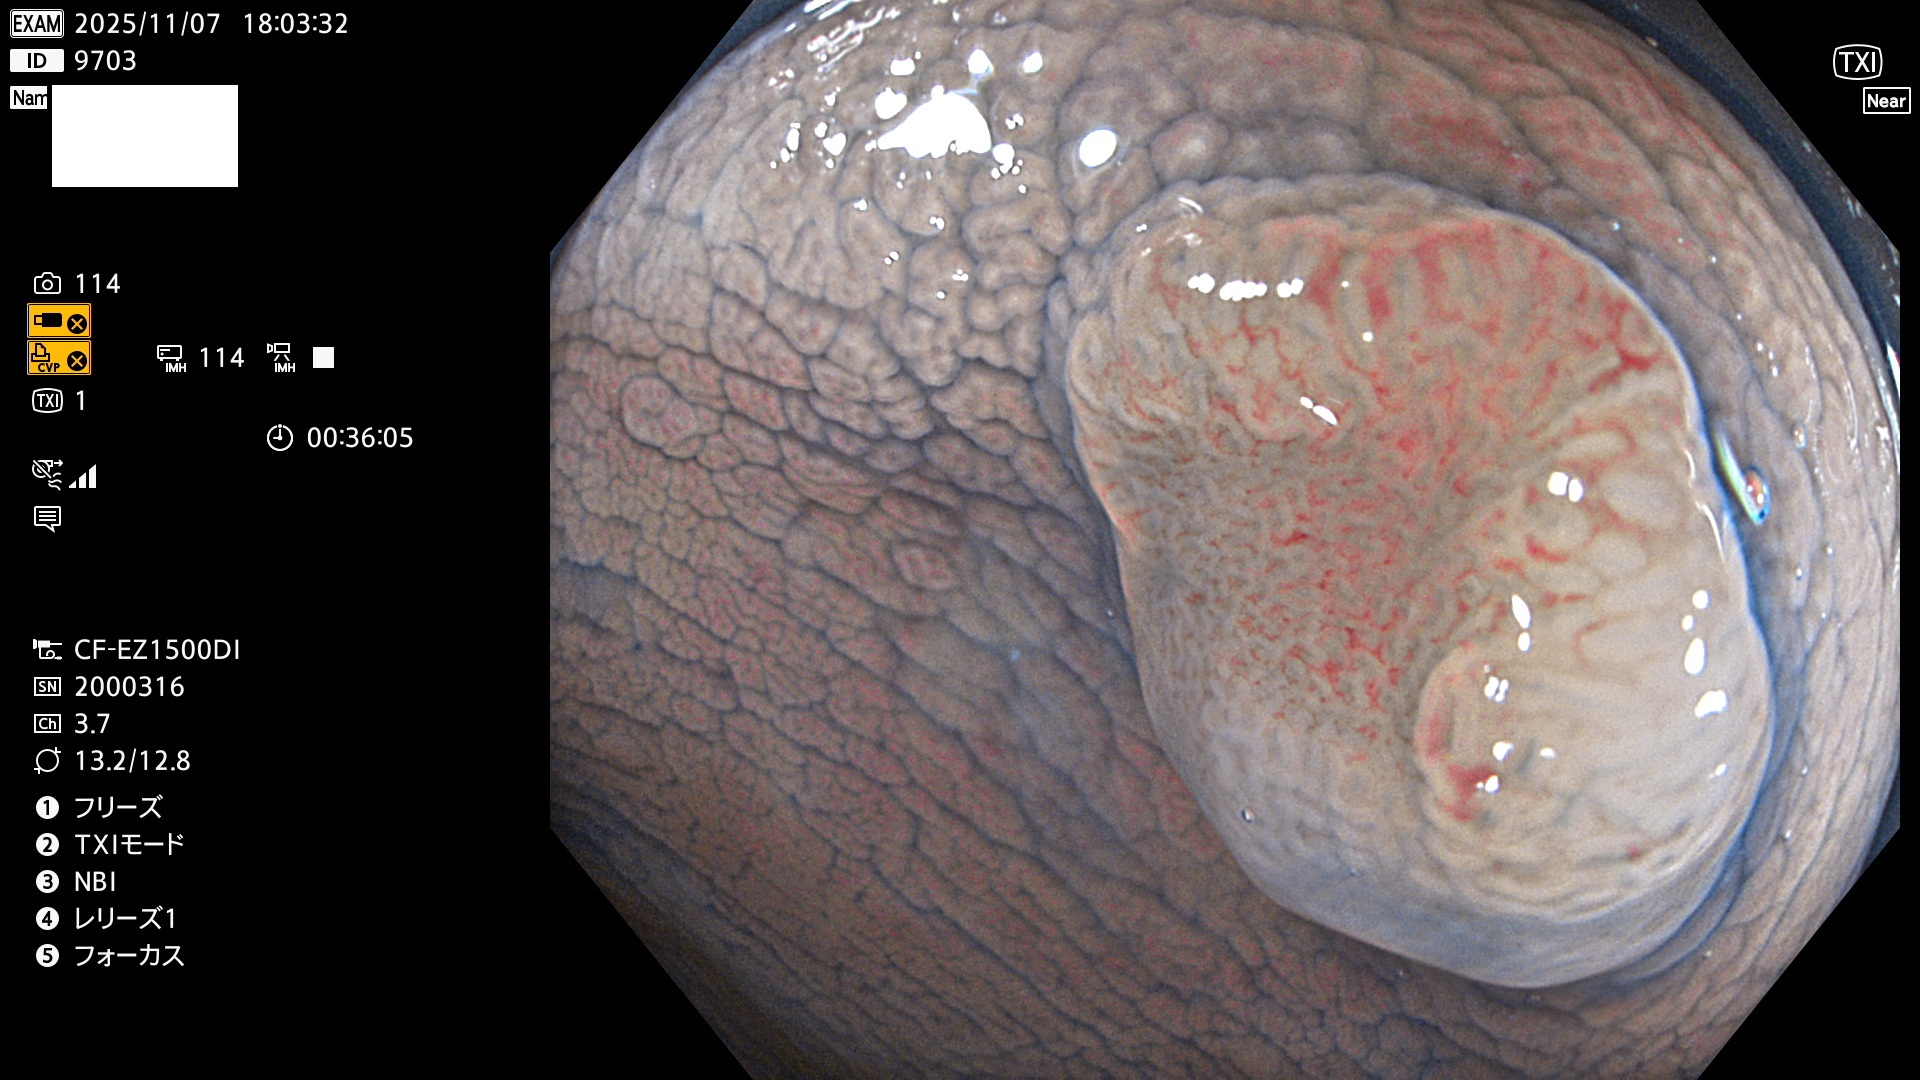

完全に平坦な物をUb、陥凹している物をUcと呼びます。Ubは認識が困難で、Ucはびらん(炎症)と紛らわしいために見落とされやすく、「内視鏡後・大腸癌」の原因になります。

専門的)細胞生物学的Ucの再定義UcをPitと形態学で定義するのは医学的には全く不毛です。Ucの本質はIntraTumor HeterogenityとTumor Dormancyが微小病変に見られる点です。これは早い腫瘍進化=ゲノム不安定性を意味します。そのような病変は隆起型でも形態によらずUcと定義すべきです。なぜなら1年後には陥凹し典型的Uc(最悪の場合NPG癌)になるからです。

2025年11月6日〜11月9日の4日間(40件)6個 (Uc_ADR=6個/40人=15%)